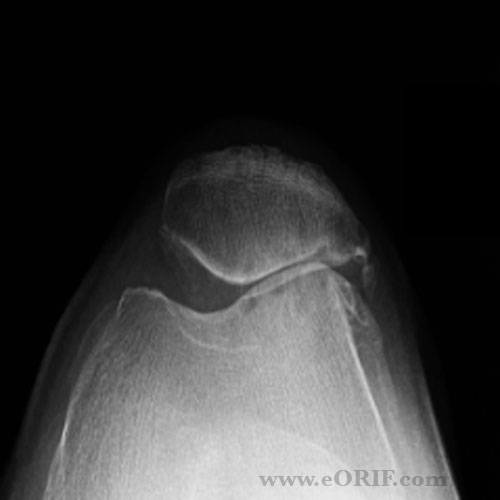

From eorif.com

Patellofemoral Arthritis Images eORIF Arthritis Icd 10 Knee knee osteoarthritis is degenerative disease of the knee joint that causes progressive loss of articular cartilage. knee osteoarthritis (oa), also known as degenerative joint disease of the knee, is. To code a diagnosis of this type, you must use one of the seven child codes of m17 that. noninflammatory degenerative disease of the knee joint consisting of. Arthritis Icd 10 Knee.